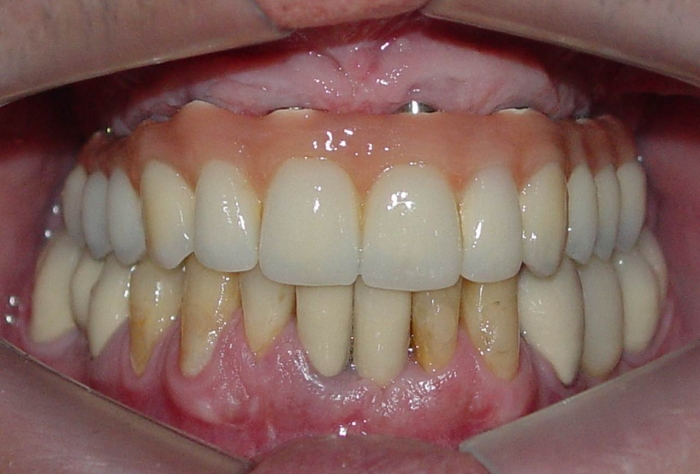

Prótese fixa em porcelana superior

Sorriso do caso terminado em abril de 2012